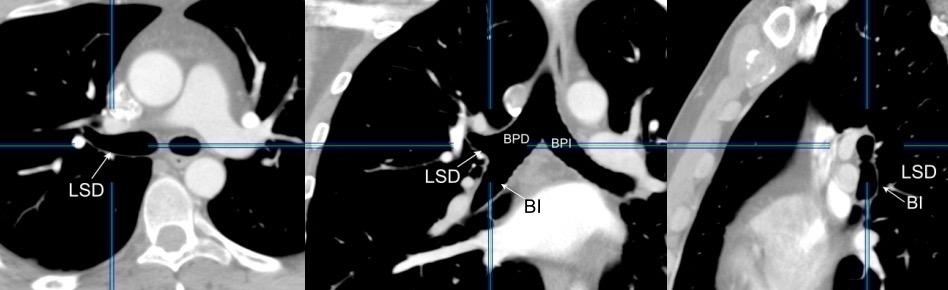

En el normal, el bronquio intermediario (BI) aparece en la proyección lateral, como una línea fina vertical que cruza el bronquio del LSI en su unión con el principal. (BPI) Engrosamiento del bronquio intermediario (BI)

97% de normales

Causas

Fallo cardiaco

Ca de pulmón

Metástasis

Linfoma

Sarcoidosis

Castleman

Schnur MJ et al.. Thickening of the Posterior Wall of the Bronchus Intermedius. Radiology. 1981

MJ et al.. Thickening of the Posterior Wall of the Bronchus Intermedius. Radiology. 1981 Ca. microcítico